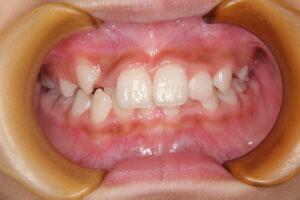

上の前歯が生え変わる小学校低学年のころに小帯が長いままでいると、前歯の間に隙間ができる原因になることがあります。これを〖正中離開〗と呼び、前歯が通常よりも離れて生えてしまう、いわゆる『すきっぱ』になるという現象です。前歯の隙間は、前歯の隣の歯や後ろの歯の生える力によって隙間が狭くなることもありますが、長いままであると完全に隙間が閉じるということはなかなか難しくなります。

上唇小帯の影響を改善するための方法としては、一般的に過剰な上唇小帯の一部を切除する手術が推奨されます。切除のタイミングは、早いに越したことはありませんが上の前歯が生え変わる7.8歳頃には切除しておくことが望ましいと思われます。この手術により、前歯の間の隙間が改善されたり上唇の動きが自由になったりします。また、手術後に歯科矯正治療を行うことにより歯並びの改善が期待されます。手術は、外来で行われることが多く、難しいものではありませんが、お口の中のすじを切除となると、怖くなってしまうお子さんがほとんどでしょう。ご本人にもきちんと説明して理解を促すことが大切です。